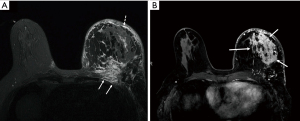

One commonality among IBC patients is a history that included evaluation with mammography that was reviewed as normal or no mass was identified. Indeed, in the study by Kamal et al., a review of images reveals that simple and malignant forms of mastitis have many signs in common (20). Mammographic signs were considered less discriminating than ultrasonography for identifying malignancy. Diffuse skin thickening and increased density favored malignant mastitis, whereas dilated retroareolar ducts and characteristic calcification patterns favored noninfectious forms. All of the patients with IBC had skin thickening on ultrasonography, but only 54% had skin thickening identified on mammography (20). However, skin thickening can also be present in benign mastitis (Figure 3). In the study by Dabi et al., the presence of a mass (present in 21/45 cases, malignant in 15/20, P=0.04), microcalcifications (present in 20/45 cases, malignant in 16/20, P=0.04) or focal asymmetry on mammography (present in 9/45 cases, malignant in 8, P<0.001) were all significantly associated with malignant disease, but these signs were not present in all cases (17). Overall, relative to patients with benign disease, patients with a malignant lesion were more likely to have skin thickening (58% vs. 32%, P=0.05) and more lymph nodes suspected of harboring disease at clinical examination (50% vs. 8%, P<0.001). Patients with malignant disease were also significantly older (P=0.022) and had significantly larger palpable masses (8.1 vs. 4.1 cm, P<0.001). Conversely, precise delimitation of the mass on ultrasonography was significantly associated with benign lesions. In work from Le-Petross et al. (21), primary breast lesions were more often visible on sonography than on mammography. An interesting sonographic feature best demonstrated on extended-field-of-view images was a linear infiltrative pattern that dissected through the breast parenchyma with loss of normal architecture (Figure 4). Critically, targeting this area of focal linear infiltration in the absence of a discrete mass on sonography yielded a diagnosis of cancer and enabled evaluation of biological markers in this study (21). Moreover, primary breast lesions on a background of extensive diffuse edema were more likely to be detected on MRI (when contrast is used) than on ultrasonography or mammography (Figure 5), and this additional information can assist in identifying a target for biopsy (21). Yang et al. reviewed and compared mammography, ultrasonography, MRI, and positron emission tomography/computed tomography (PET/CT) for their ability to identify breast parenchymal lesions, both to aid in the radiographic diagnosis and to guide clinicians regarding definitive biopsy (22). Among the 80 patients included in that study, 75 (94%) had undergone mammography, 76 (95%) sonography, 33 (41%) MRI with contrast, and 24 (30%) PET/CT. A primary parenchymal breast lesion was found in 60 patients (80%) on mammography (mass or calcifications), 72 (95%) on sonography (mass or architectural distortion), 23 (96%) on PET/CT (hypermetabolic lesion), and 33 (100%) on MRI (enhancing lesion). These findings highlight the value of MRI in the work-up of IBC to guide biopsy when earlier imaging has failed to reveal a dominant lesion or shows abnormal but inconclusive results. Notably, 97% of the women in this study had non-fatty breasts despite being largely postmenopausal. The authors speculate that the breast parenchymal background may have contributed to the poor visibility of a primary breast parenchymal lesion on mammography in 15 patients (20%). Also, the basic imaging findings associated with IBC in that study agreed with those described by others (23-30), namely, diffusely increased parenchymal density (now termed global asymmetry according to the ACR BIRADS lexicon (31), trabecular distortion, and skin thickening on mammography. The same group undertook an expanded analysis focusing on MRI and identified a very high likelihood of detecting a breast parenchymal lesion with MRI (98%, n=80) compared with 68% on mammography. Among patients with a breast parenchymal lesion, the most common MRI finding was a mass or multiple masses (57 of 78, 73%) (22). Masses were often multiple, small, and confluent (47 of 57, 82%); mass margins were irregular (43 of 57, 75%); and had a heterogeneous internal enhancement pattern (47 of 57, 82%). Kinetic analysis revealed a delayed washout pattern in 66 of 78 tumors (85%). MRI showed skin thickening in 74 of 80 breasts (93%), whereas mammography showed skin thickening in 56 of 78 breasts (72%) (22).

The edema component of IBC is well demonstrated on the T2-weighted images of a standard MRI examination (Figure 5), triggering some investigators to assess the value of this edema to distinguish benign inflammation from malignant inflammation or its predictive potential if the edema resolved. Kanao et al. retrospectively reviewed 162 patients presenting with inflammatory breast symptoms who underwent breast MRI [T2-weighted imaging, with diffusion weighted imaging (DWI) or dynamic contrast-enhanced (DCE) imaging] from 2008 through 2015. Among breast lesions with high-T2-signal intensity, 14 were benign inflammatory lesions, 69 were benign non-inflammatory lesions, 16 were malignant inflammatory lesions, and 63 were malignant non-inflammatory lesions (32). Notably, segmentation of those breast lesions having high T2 signals [by apparent diffusion coefficient (ADC) mapping, which is derived from T2-weighted images and DWI] could distinguish benign from malignant inflammatory conditions, but ADC mapping of low-T2-signal areas did not (32). In another evaluation of MRI, Harada et al. evaluated a model of breast edema scores in 408 women with breast cancer and found that the edema detectable on T2-weighted images was related to prognosis after neoadjuvant chemotherapy (13).